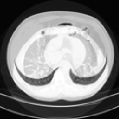

IV-F1 GeMix leads to more realistic images

One of our hypotheses is that GeMix is supposed to lead to more realistic images than traditional mixup or MMixup. Figure 2 illustrates a few examples produced by mixup (first column), MMixup (second column) and GeMix (third column). We observe that GeMix produces more anatomically coherent images, whereas the interpolation in pixel-space performed by mixup and MMixup leads to images that are not anatomically valid.